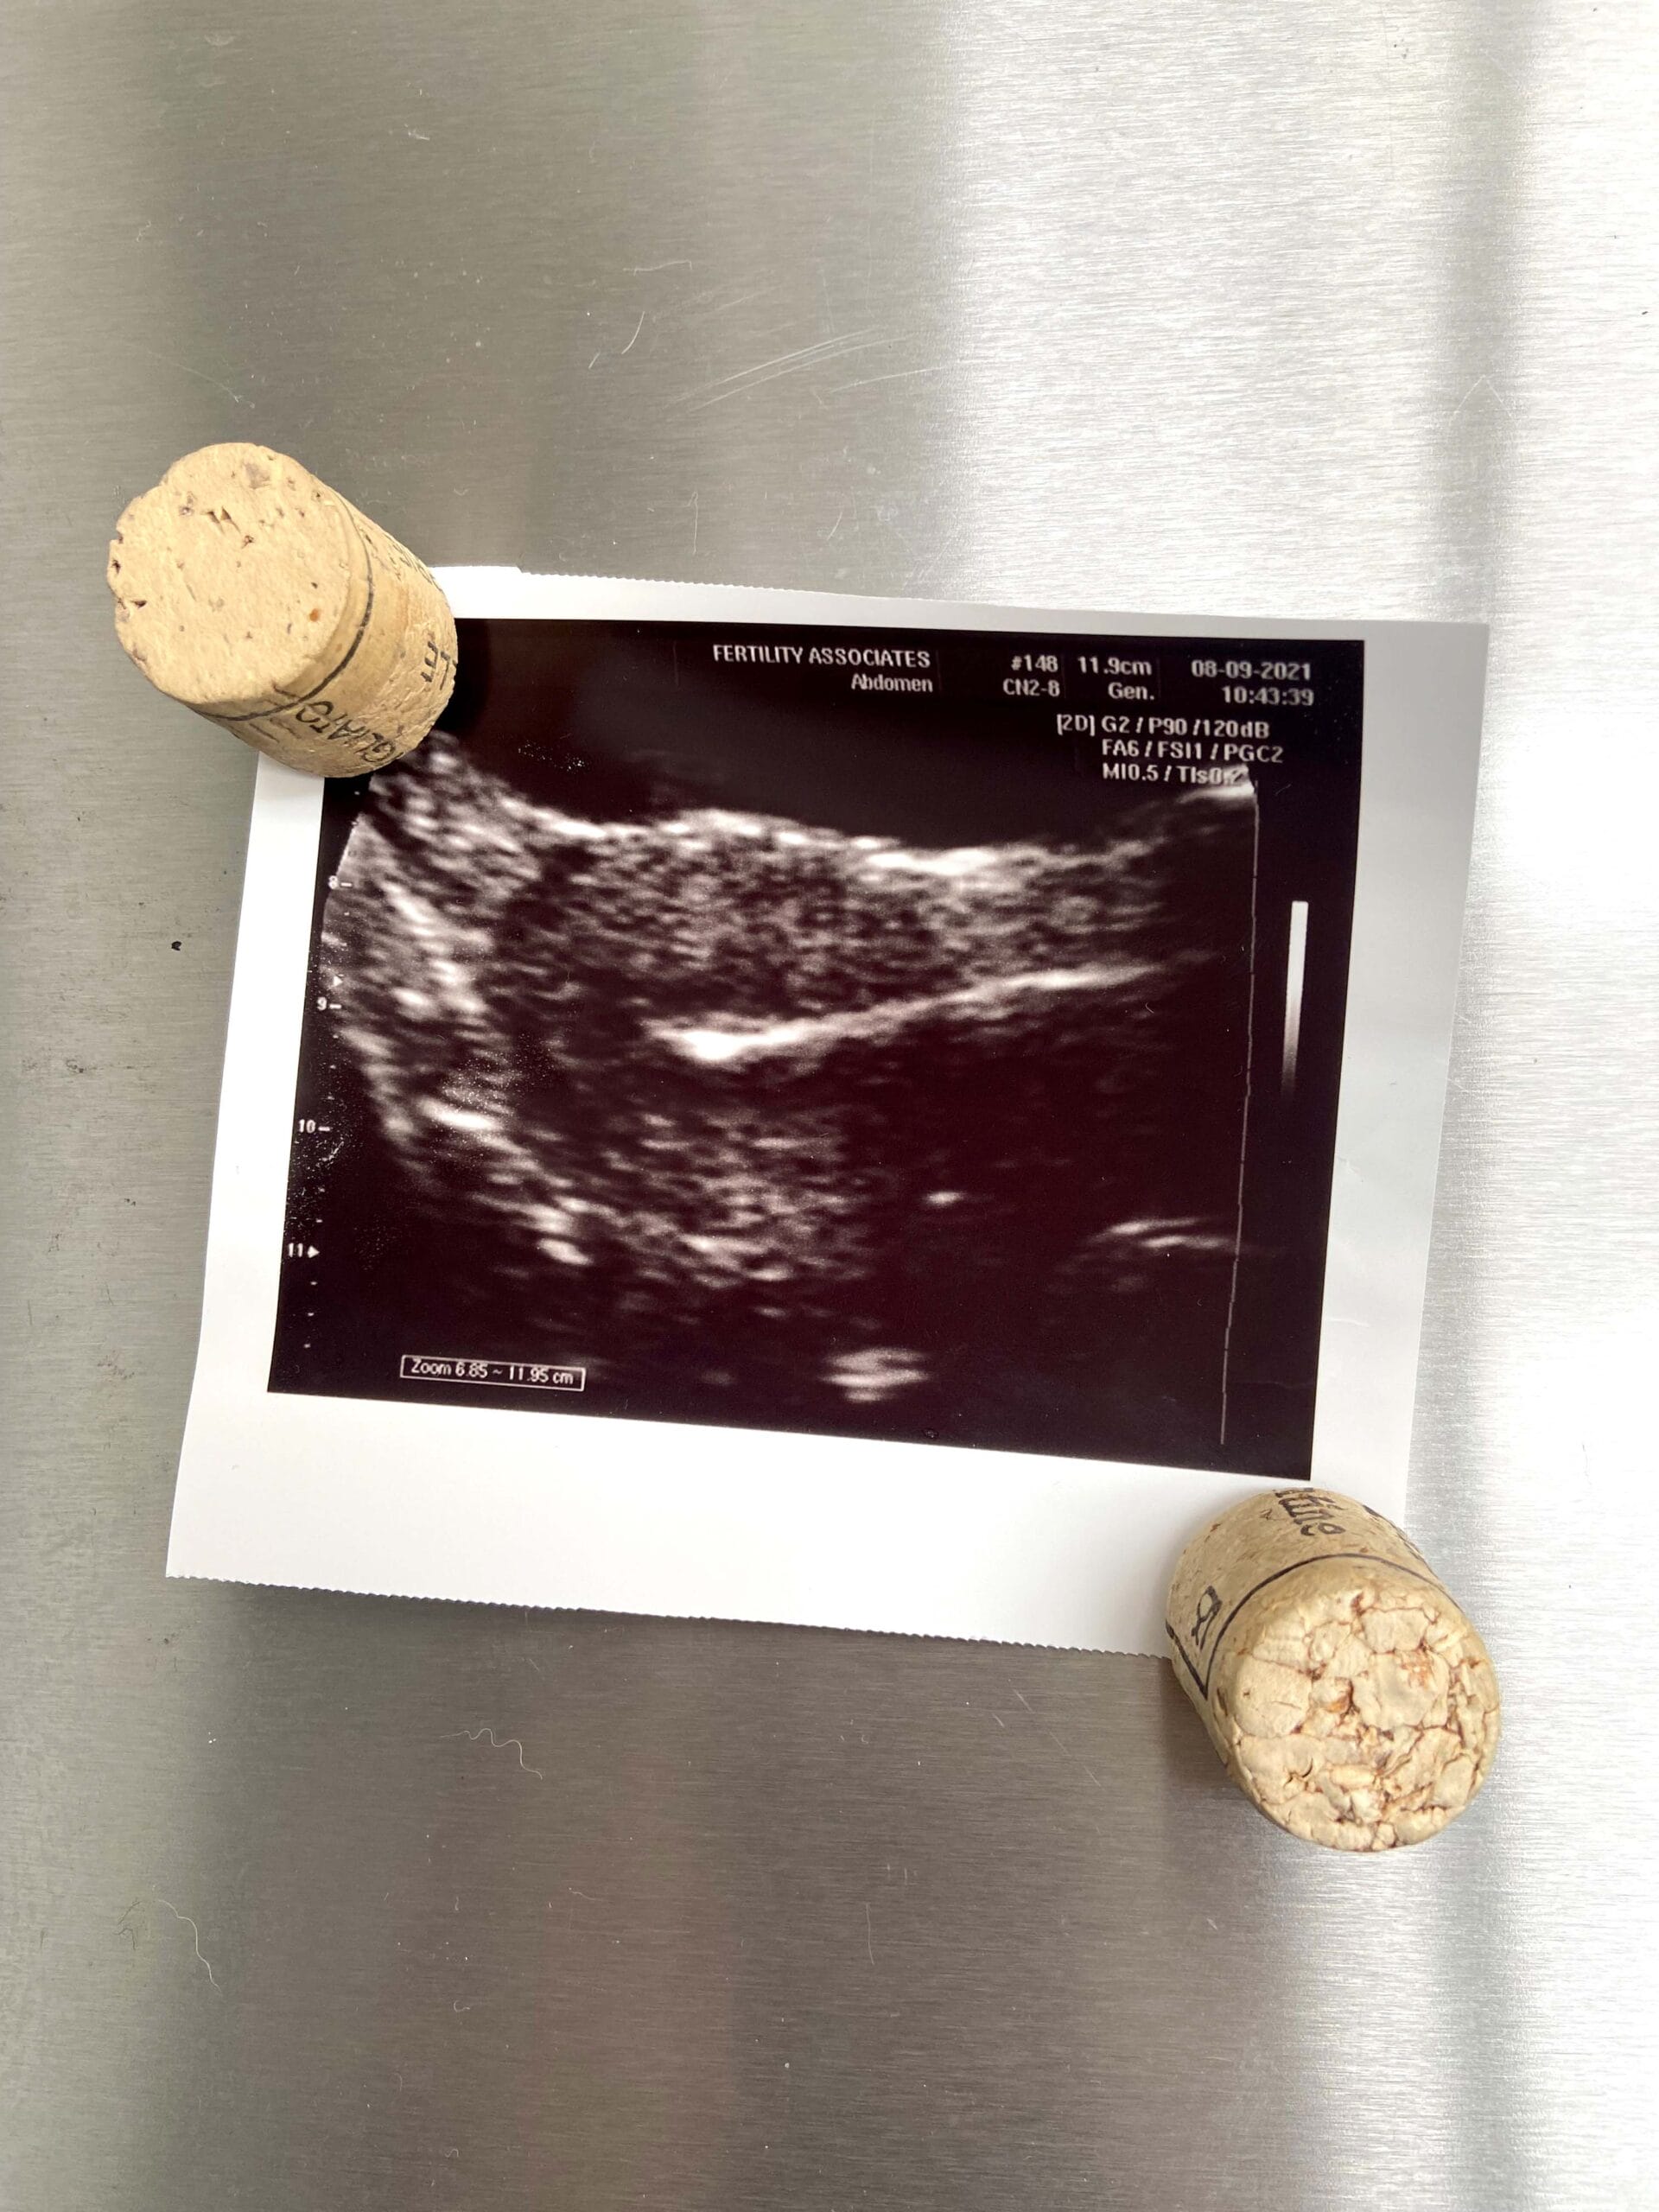

It becomes less easy to detach when, on the screen, a sudden flash of light bursts into the inky black empty space of my womb. I’m mesmerised as they play my embryo’s dramatic starburst appearance over and over on the screen, as if the ref is trying to decide whether a try has been scored.

They print me out a little Polaroid of my shooting star to take home, like a party memento.

I put my “baby” picture on the fridge, which I’m visiting often because, well, lockdown. But while I’m there, I look at it and think, “What if…?”

I stare at my little Polaroid on the fridge and think about how miraculous it is that any of us are here, given the frailties of the human reproductive process.

I take my Polaroid off the fridge.